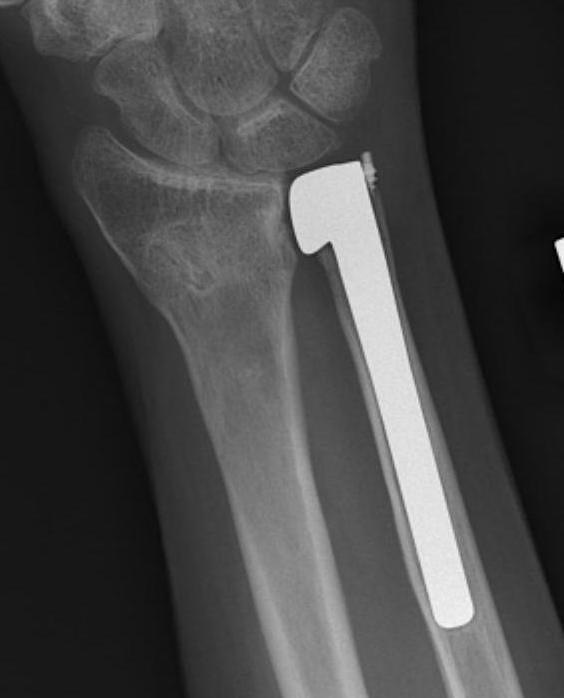

Suav-Kapanji

Technique

- distal radio-ulna arthrodesis with distal ulna pseuodoarthrosis

- distal ulna fused to distal radius with 2 screws

- distal ulna stabilised with half FCU

- interposition with pronator quadratus